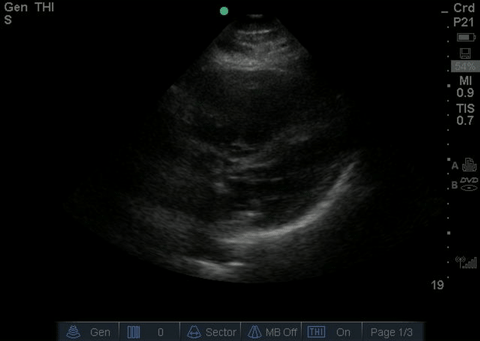

Normal subxiphoid/subcostal view

| current | 13:07, 18 July 2016 | 480 × 341 (1.39 MB) | Neil.m.young (talk | contribs) | Normal subxiphoid/subcostal view |